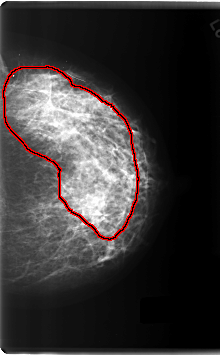

FILE: C_0203_1.LEFT_CC.OVERLAY

TOTAL_ABNORMALITIES 1

ABNORMALITY 1

LESION_TYPE CALCIFICATION TYPE PLEOMORPHIC DISTRIBUTION REGIONAL

ASSESSMENT 5

SUBTLETY 5

PATHOLOGY MALIGNANT

TOTAL_OUTLINES 1

BOUNDARY